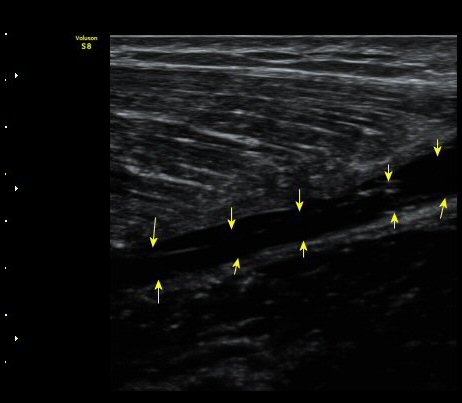

ºñº¹±Ù Ⱦ´Ü¸é°Ë»ç¿¡¼­ ºñº¹±Ù ³»Ãø, °¡Àڹٰ̱ú Á¢ÇÕ ºÎÀ§ÀÇ ÆÄ¿­°ú ¼ö¾× Àú·ù°¡ °üÂûµÊ(±×¸² 4)